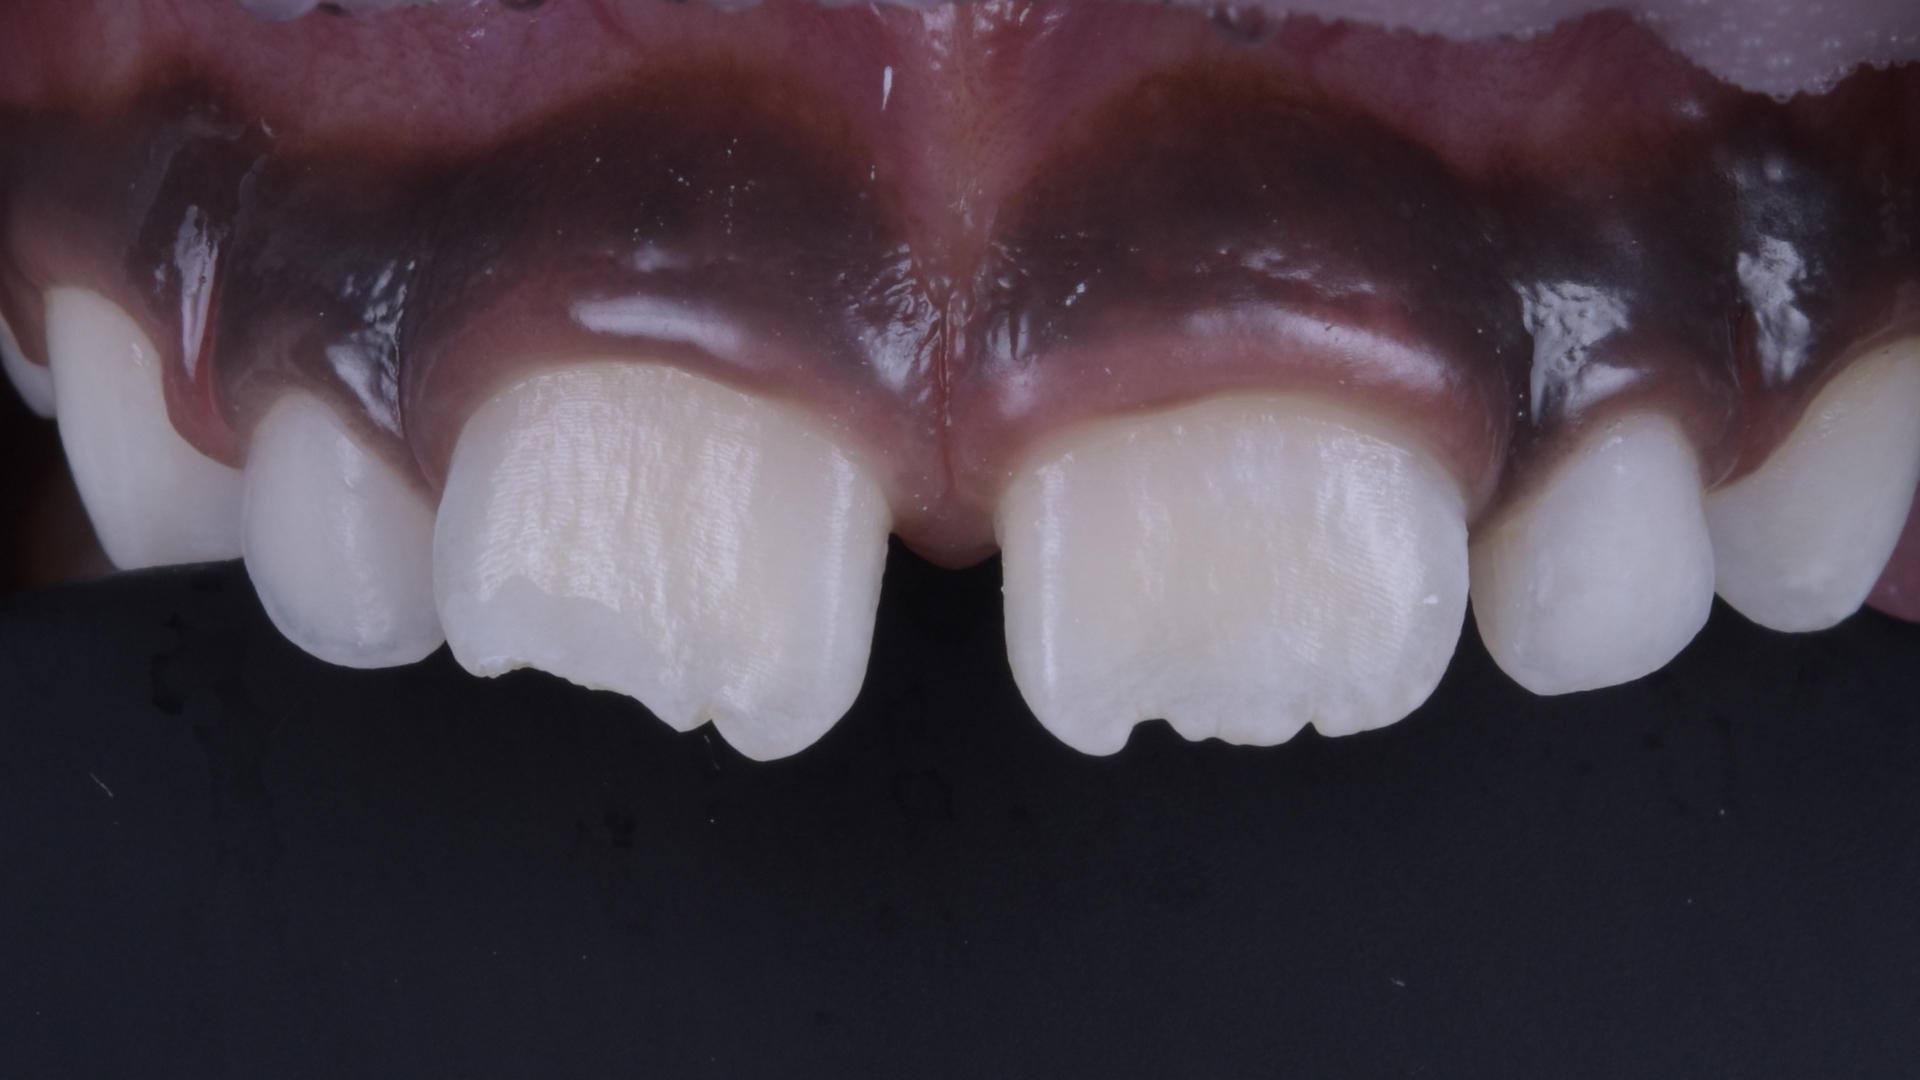

Behandlungsergebnis.

Ansicht des Zahnes 11 von lateral.